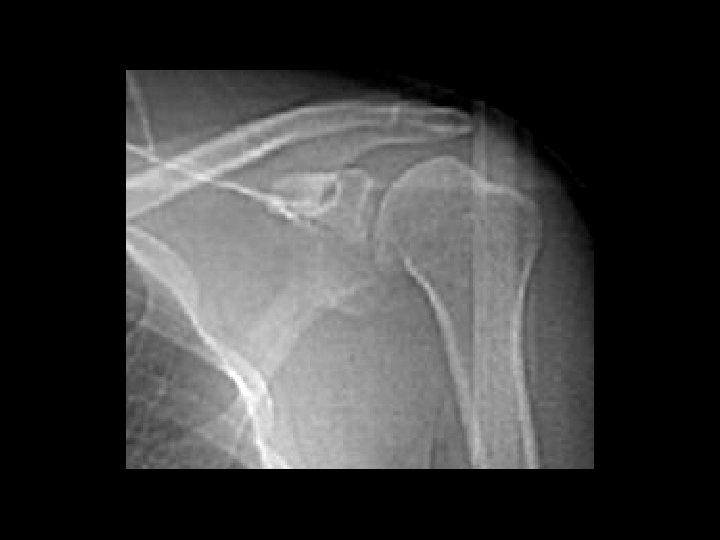

Hill-Sachs Deformity and Osseous Bankart Lesion • • • Findings: – Impaction fracture of the posterolateral humeral margin (Hill -Sachs) – Fracture of the osseous glenoid rim (Bankart) – secondary osteoarthritis Related to repeated anterior dislocations (shoulder instability) Bankart lesion is typically only of the cartilaginous labrum, best seen on MRI